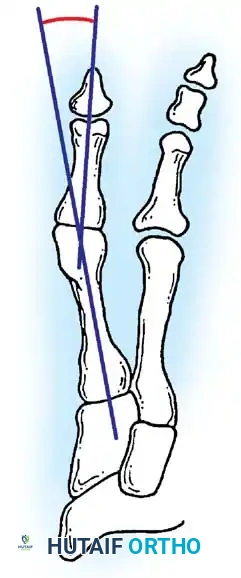

Inadequate vascularity or sensibility should be investigated thoroughly before bunion surgery is considered. In addition, the position of the articular surface of the metatarsal head in relation to the longitudinal axis of the fi rst metatarsal should be determined (Fig. 78-8). Standard preoperative radiographs should include standing dorsoplantar and lateral views, a nonstanding lateral oblique view, and axial sesamoid views (Fig. 78-9). The hallux valgus angle and the fi rst-second intermetatarsal angle should fi rst be drawn on the standing dorsoplantar view by bisecting the shafts of the bones (Fig. 78-10), with an awareness of the normal ranges. These angles are most frequently cited as guidelines for treatment decisions, but Donnelly et al. reported that interobserver measurements of the hallux valgus angle varied by approximately 6 degrees and of the intermetatarsal angle by 4 degrees. They cautioned that potential errors in measurement should be considered when these parameters are used to make treatment decisions. The hallux valgus interphalangeus angle and any evidence of degenerative arthritic changes at the fi rst metatarsophalangeal or metatarsocuneiform joints should be documented. Oddities may be present and, if overlooked, may compromise a technically well-done procedure. Mann emphasized that the presence of an os inter-

A B

Fig. 78-8 A, Determination of position of articular surface of metatarsal head in relation to longitudinal axis of fi rst metatarsal. B, Measurement of distal metatarsal articular angle at time of surgery. Markings are at medial and lateral margins of articular surface of fi rst metatarsal head and longitudinal axis of fi rst metatarsal shaft. metatarseum between the bases of the fi rst and second metatarsals might preclude the effectiveness of a soft-tissue procedure alone to provide suffi cient correction of the increased intermetatarsal angle. Likewise, accessory sesamoids and prominent ungual tuberosities at the interphalangeal joint contribute to a painful callus at the tibial side of this joint. An os tibialis externum frequently is associated with excessive hallux valgus interphalangeus. Varus of the fi rst metatarsal might be a signifi cant part of the overall deformity of the foot even with an intermetatarsal angle of less than 10 degrees. Metatarsus varus with a relatively small hallux valgus angle (15 to 20 degrees) may produce signifi cant deformity even though the angles are not excessive. The usefulness of computer-assisted compared with manual measurement of the intermetatarsal angle, hallux valgus angle, and distal metatarsal articular angle is still uncertain. Both methods have closer interobserver and intraobserver correlation in measurement of the intermetatarsal angle and hallux valgus angle than in measurement of the distal metatarsal articular angle. The reliability of either method has such a wide range (5 degrees), however, that measurements of these angles, although useful as a guide, do not provide a completely reliable indication of the magnitude of deformity. Condon et al. suggested that the reliability of the intermetatarsal angle can be improved by careful technique and by making the measurements at least twice and averaging them. Schneider et al. reported two methods of determining angular measurements based on distinctly different reference points: (1) a longitudinal axis of the fi rst metatarsal using middiaphyseal reference points, and (2) a center-head technique using a center head (center of the articular surface) and center base

(center of the proximal diaphysis) as reference points. They found that measured correction of the hallux valgus and intermetatarsal angles varied by approximately 9 degrees depending on which reference points were used. Recommendations of Coughlin, Saltzman, and Nunley (American Orthopaedic Foot and Ankle Society Ad Hoc Committee on Angular Measurements) included standardized radiographic technique, specifi c placement of reference points (Fig. 78-11), use of a protractor rather than a goniometer for measurements, and, after distal osteotomies, dual measurements using a center-head technique and a Mose sphere.